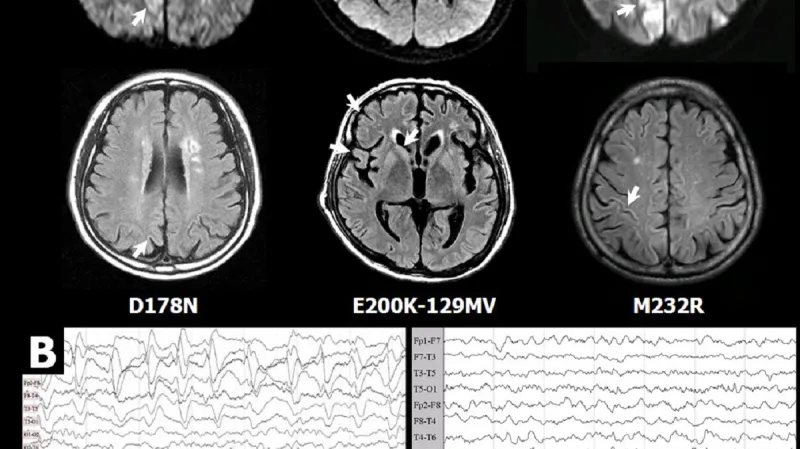

Tato choroba zasáhla jen minimum lidí; o něco větším problémem se stala Creutzfeld-Jakobova choroba. Tu popsali němečtí lékaři mezi dvěma světovými válkami a stále proti ní neexistuje lék. Nejčastěji se projeve v těsně předdůchodovém věku a do necelého roka přináší smrt. Naštěstí je velice vzácná, objevuje se přibližně u jednoho člověka z milionu.

Všechny nemoci způsobované priony mají podobný průběh: nejprve se u člověka zhoršuje koordinace pohybu, přicházejí poruchy s pamětí a zraku. Postupně přibývají další symptomy jako demence, neovladatelné pohyby, změny chování. V posledních fázích života je mozek už natolik poškozený, že přichází slepota, slabost a kóma následované smrtí.

Jenže někdy se může prostorově nastavit špatně; a pak může způsobovat problémy. Takto zašmodrchané priony se hromadí v tkáni a způsobují její degeneraci. V mozku získává tkáň typicky houbovitou podobu – právě podle ní se těmto prionovým nemocem říká spongiformní (houbotvará) encefalopatie.